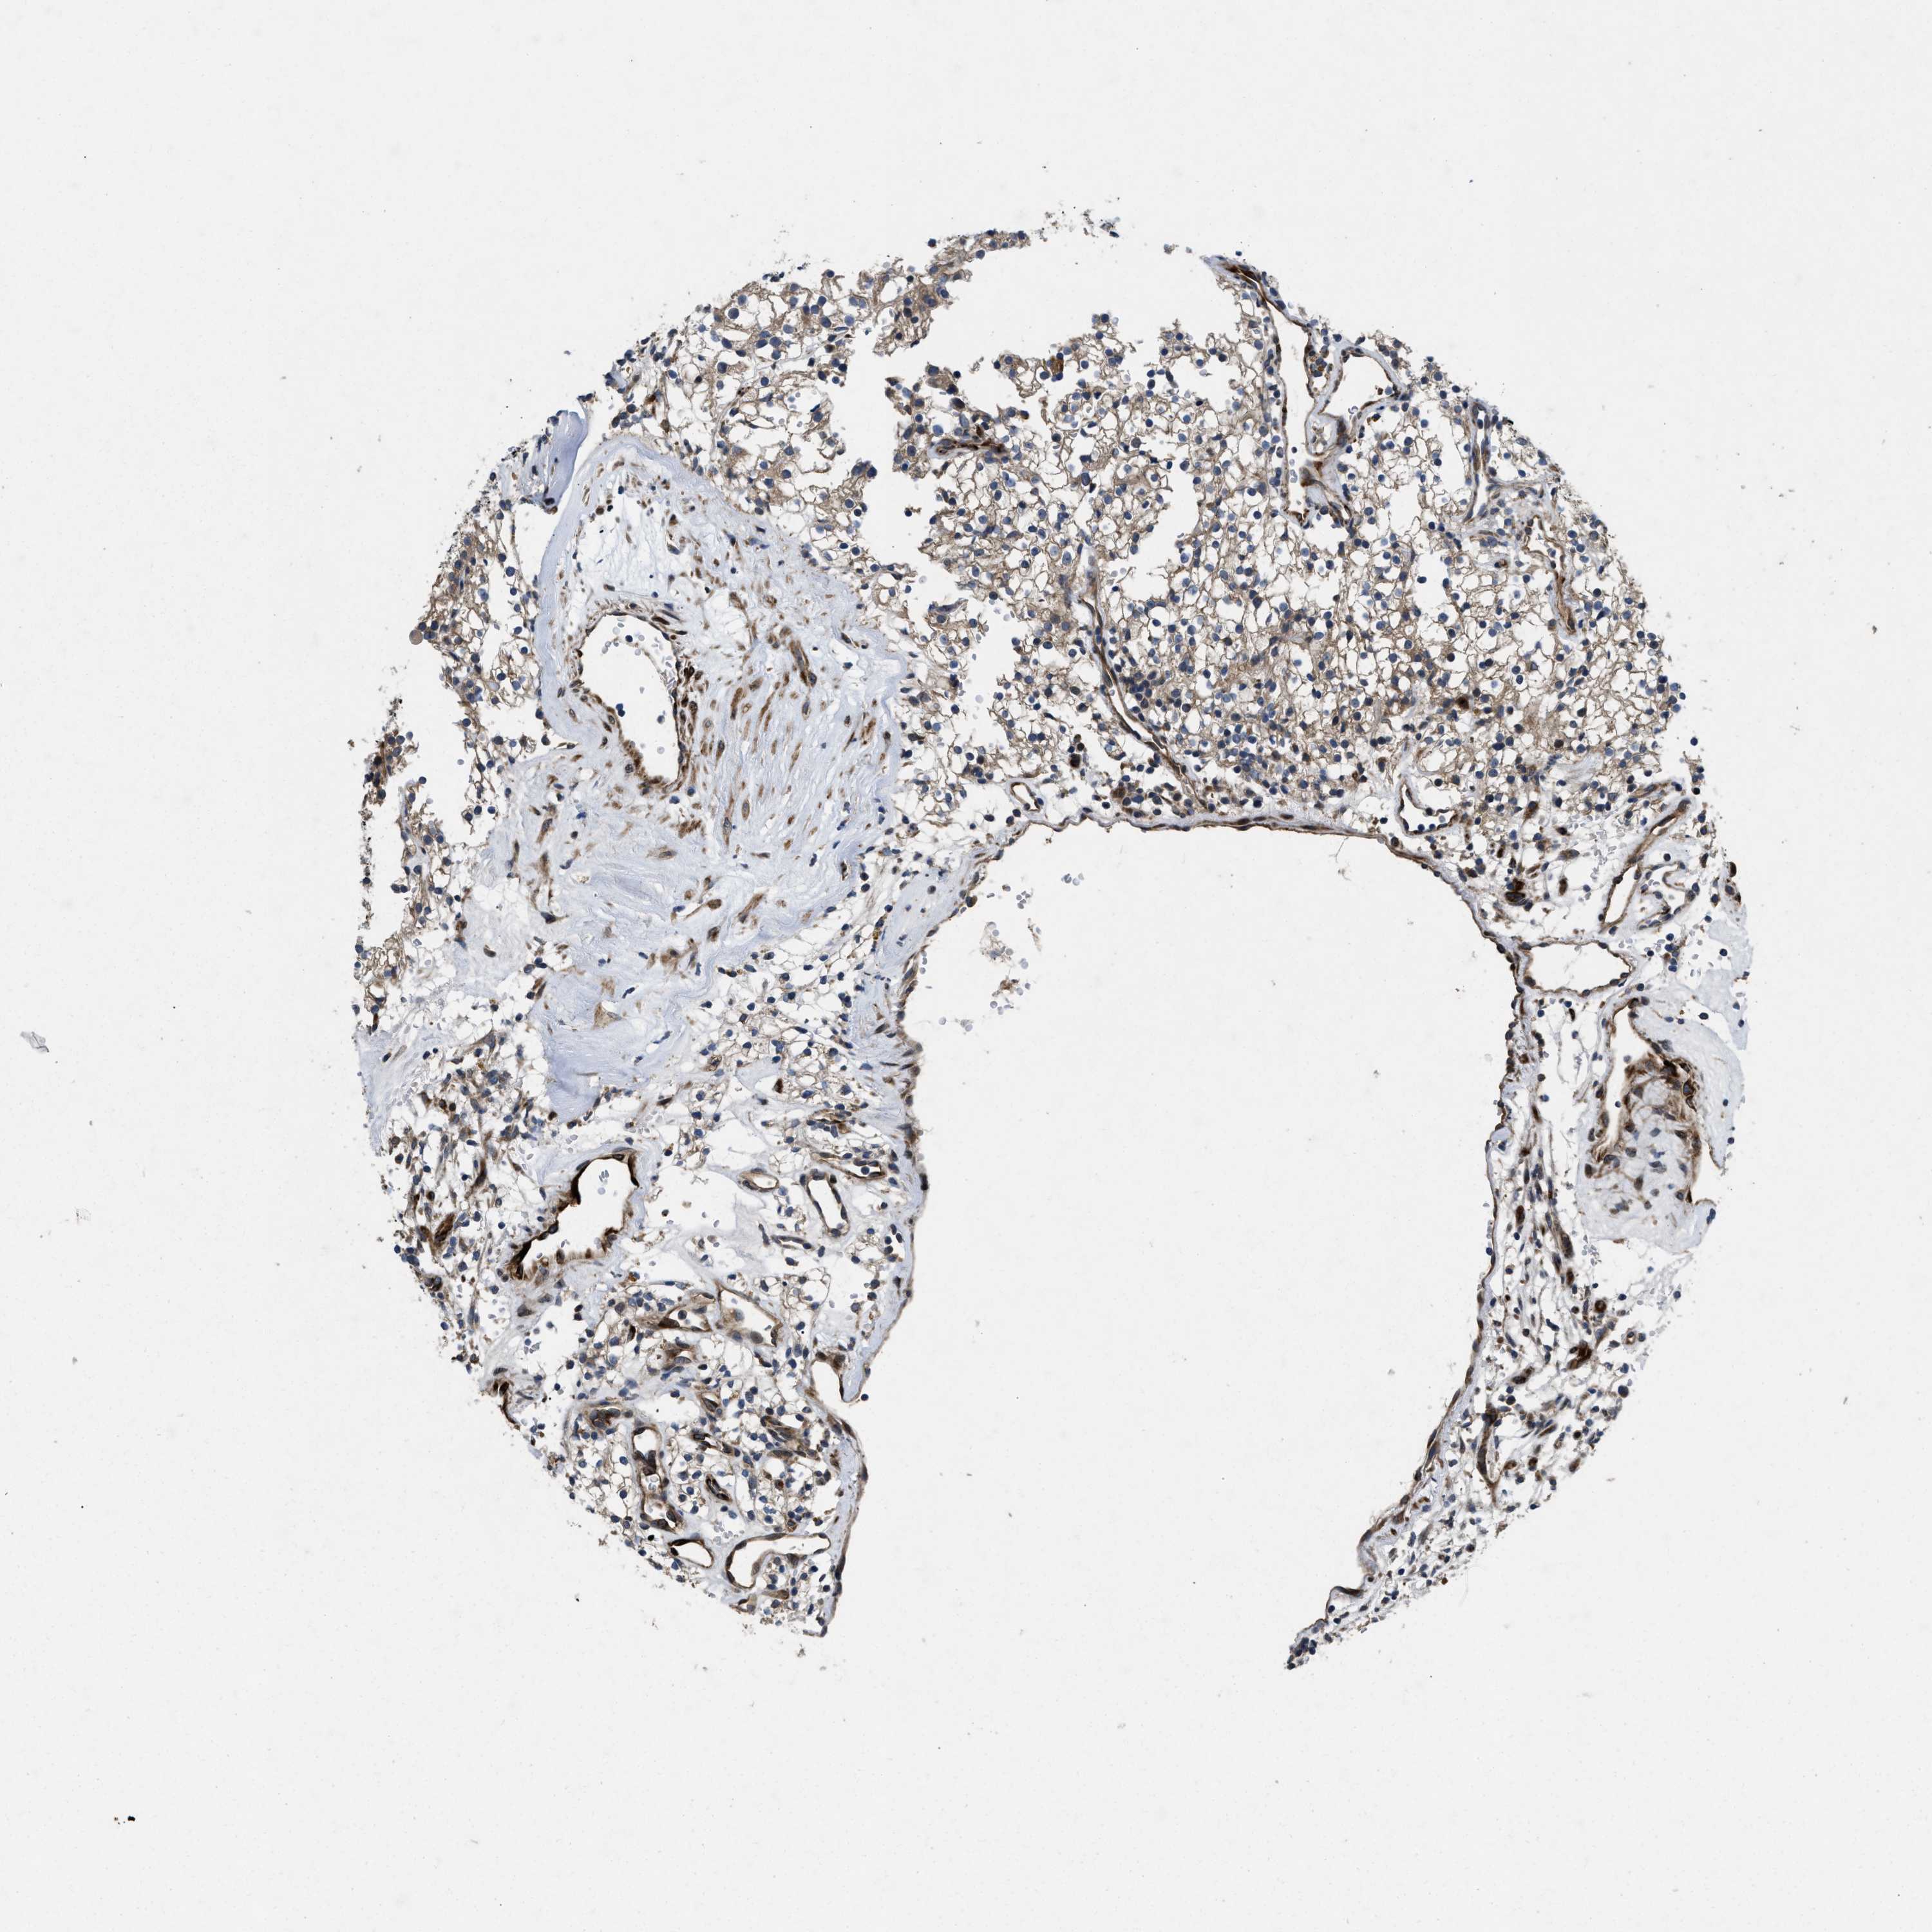

KIDNEY RENAL PAPILLARY CELL CARCINOMA (TCGA) - Interactive survival scatter ploti

The Survival Scatter plot shows the clinical status (i.e. dead or alive) for all individuals in the patient cohort, based on the same data that underlies the corresponding Kaplan-Meier plots. Patients that are alive at last time for follow-up are shown in blue and patients who have died during the study are shown in red.

The x-axis shows the expression levels (FPKM) of the investigated gene in the tumor tissue at the time of diagnosis. The y-axis shows the follow-up time after diagnosis (years). Both axes are complimented with kernel density curves demonstrating the data density over the axes. The top density plot shows the expression levels (FPKM) distribution among dead (red) and alive patients (blue). The right density plot shows the data density of the survived years of dead patients with high and low expression levels respectively, stratified using the cutoff indicated by the vertical dashed line through the Survival Scatter plot. This cutoff is automatically defined based on the FPKM cutoff that minimizes the p-score. The cutoff can be changed by dragging the vertical line or by entering a cutoff value in the square labeled "Current cut-off".

Under the Survival Scatter plot the p-score landscape (black curve; left axis) is shown together with dead median separation (red curve; right axis). Dead median separation is the difference in median mRNA expression between patients who have died with high and low expression, respectively. It is calculated as follows: median FPKM expression of dead patients with high expression - median FPKM expression of dead patients with low expression. This is intended to aid the user in visually exploring custom cutoffs and the associated p-scores and dead median separation.

Individual patient data is displayed and can be filtered by clicking on one or more of the category buttons on the top of the page. Categories describing expression level and patient information include: high, low, alive, dead, female, male and tumor stages. The scale of the x-axis can be toggled between linear and log-scale by clicking on the "x log" button. Mouse-over function shows TCGA ID, patient information and mRNA expression (FPKM) for each patient.

& Survival analysisi

Kaplan-Meier plots summarize results from analysis of correlation between mRNA expression level and patient survival. Patients were divided based on level of expression into one of the two groups "low" (under cut off) or "high" (over cut off). X-axis shows time for survival (years) and y-axis shows the probability of survival, where 1.0 corresponds to 100 percent.

HSPA12B is not prognostic in Kidney Renal Papillary Cell Carcinoma (TCGA)